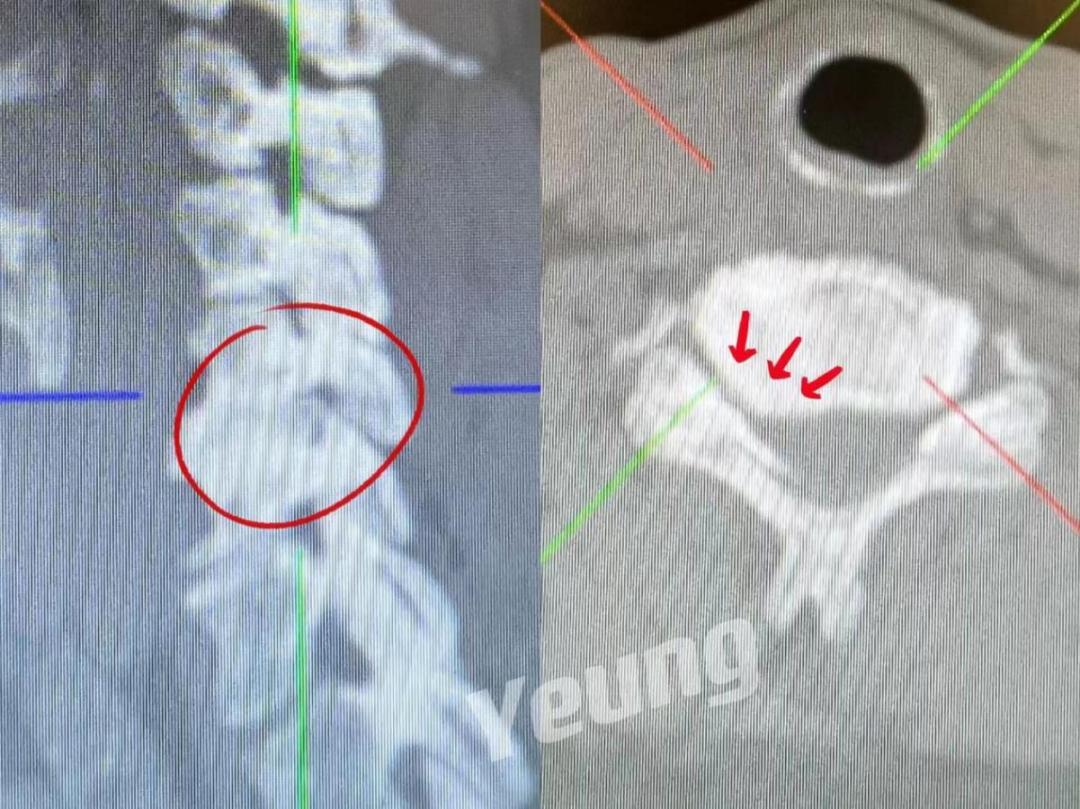

杨俊松副主任医师接诊后结合患者病史、体征和影像学资料指出,患者椎间盘突出钙化形成骨赘+神经根明显受压+椎间孔高度塌陷,建议手术干预。

脊柱病医院院长郝定均及脊柱病医院腰椎病区主任刘团江查房后指出:患者骨赘生长及神经根受压明显,且曾有过两次甲状腺手术经历,建议采用内镜下的颈椎后路keyhole手术。